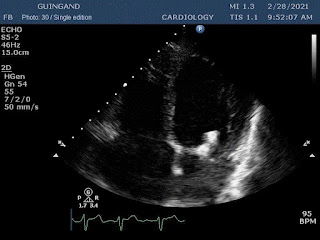

These are the first Cardiology NFTs for sale on a marketplace.

37 unique photos of the artist's most recent echocardiogram.

“Art is inside of us too.”